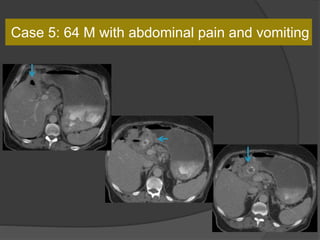

Case 5: 64 M with abdominal pain and vomiting

Dx: Cholecystogastric fistula with gastric outlet obstruction

Gastric outlet obstruction caused by a large gallstone

passing into the duodenal bulb through a biliogastric or

bilioduodenal fistula.

What is it called?

Bouveret's syndrome